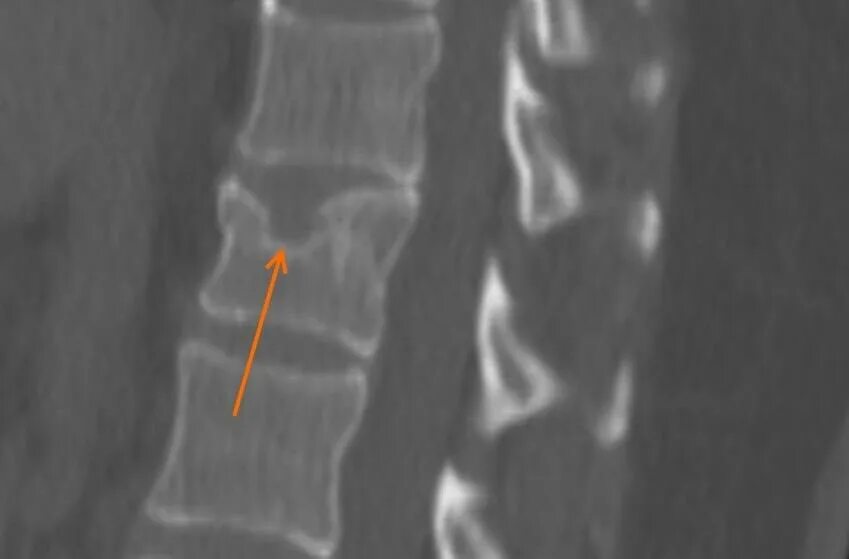

Протрузии шморля